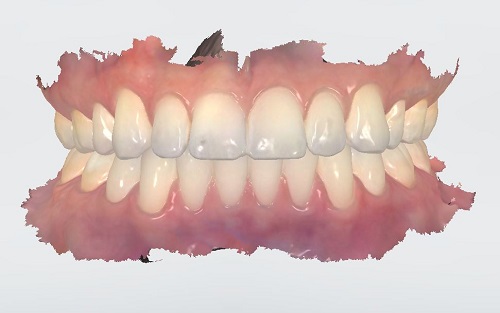

They took this wand-like thing and spent some time running it over my teeth. You end up getting a picture that looks something like this:

Of course, those teeth look a lot better than mine.

They can look at just the top teeth or the bottom teeth. They can twist it and turn it around on the screen and see behind them and everything. It was pretty cool.